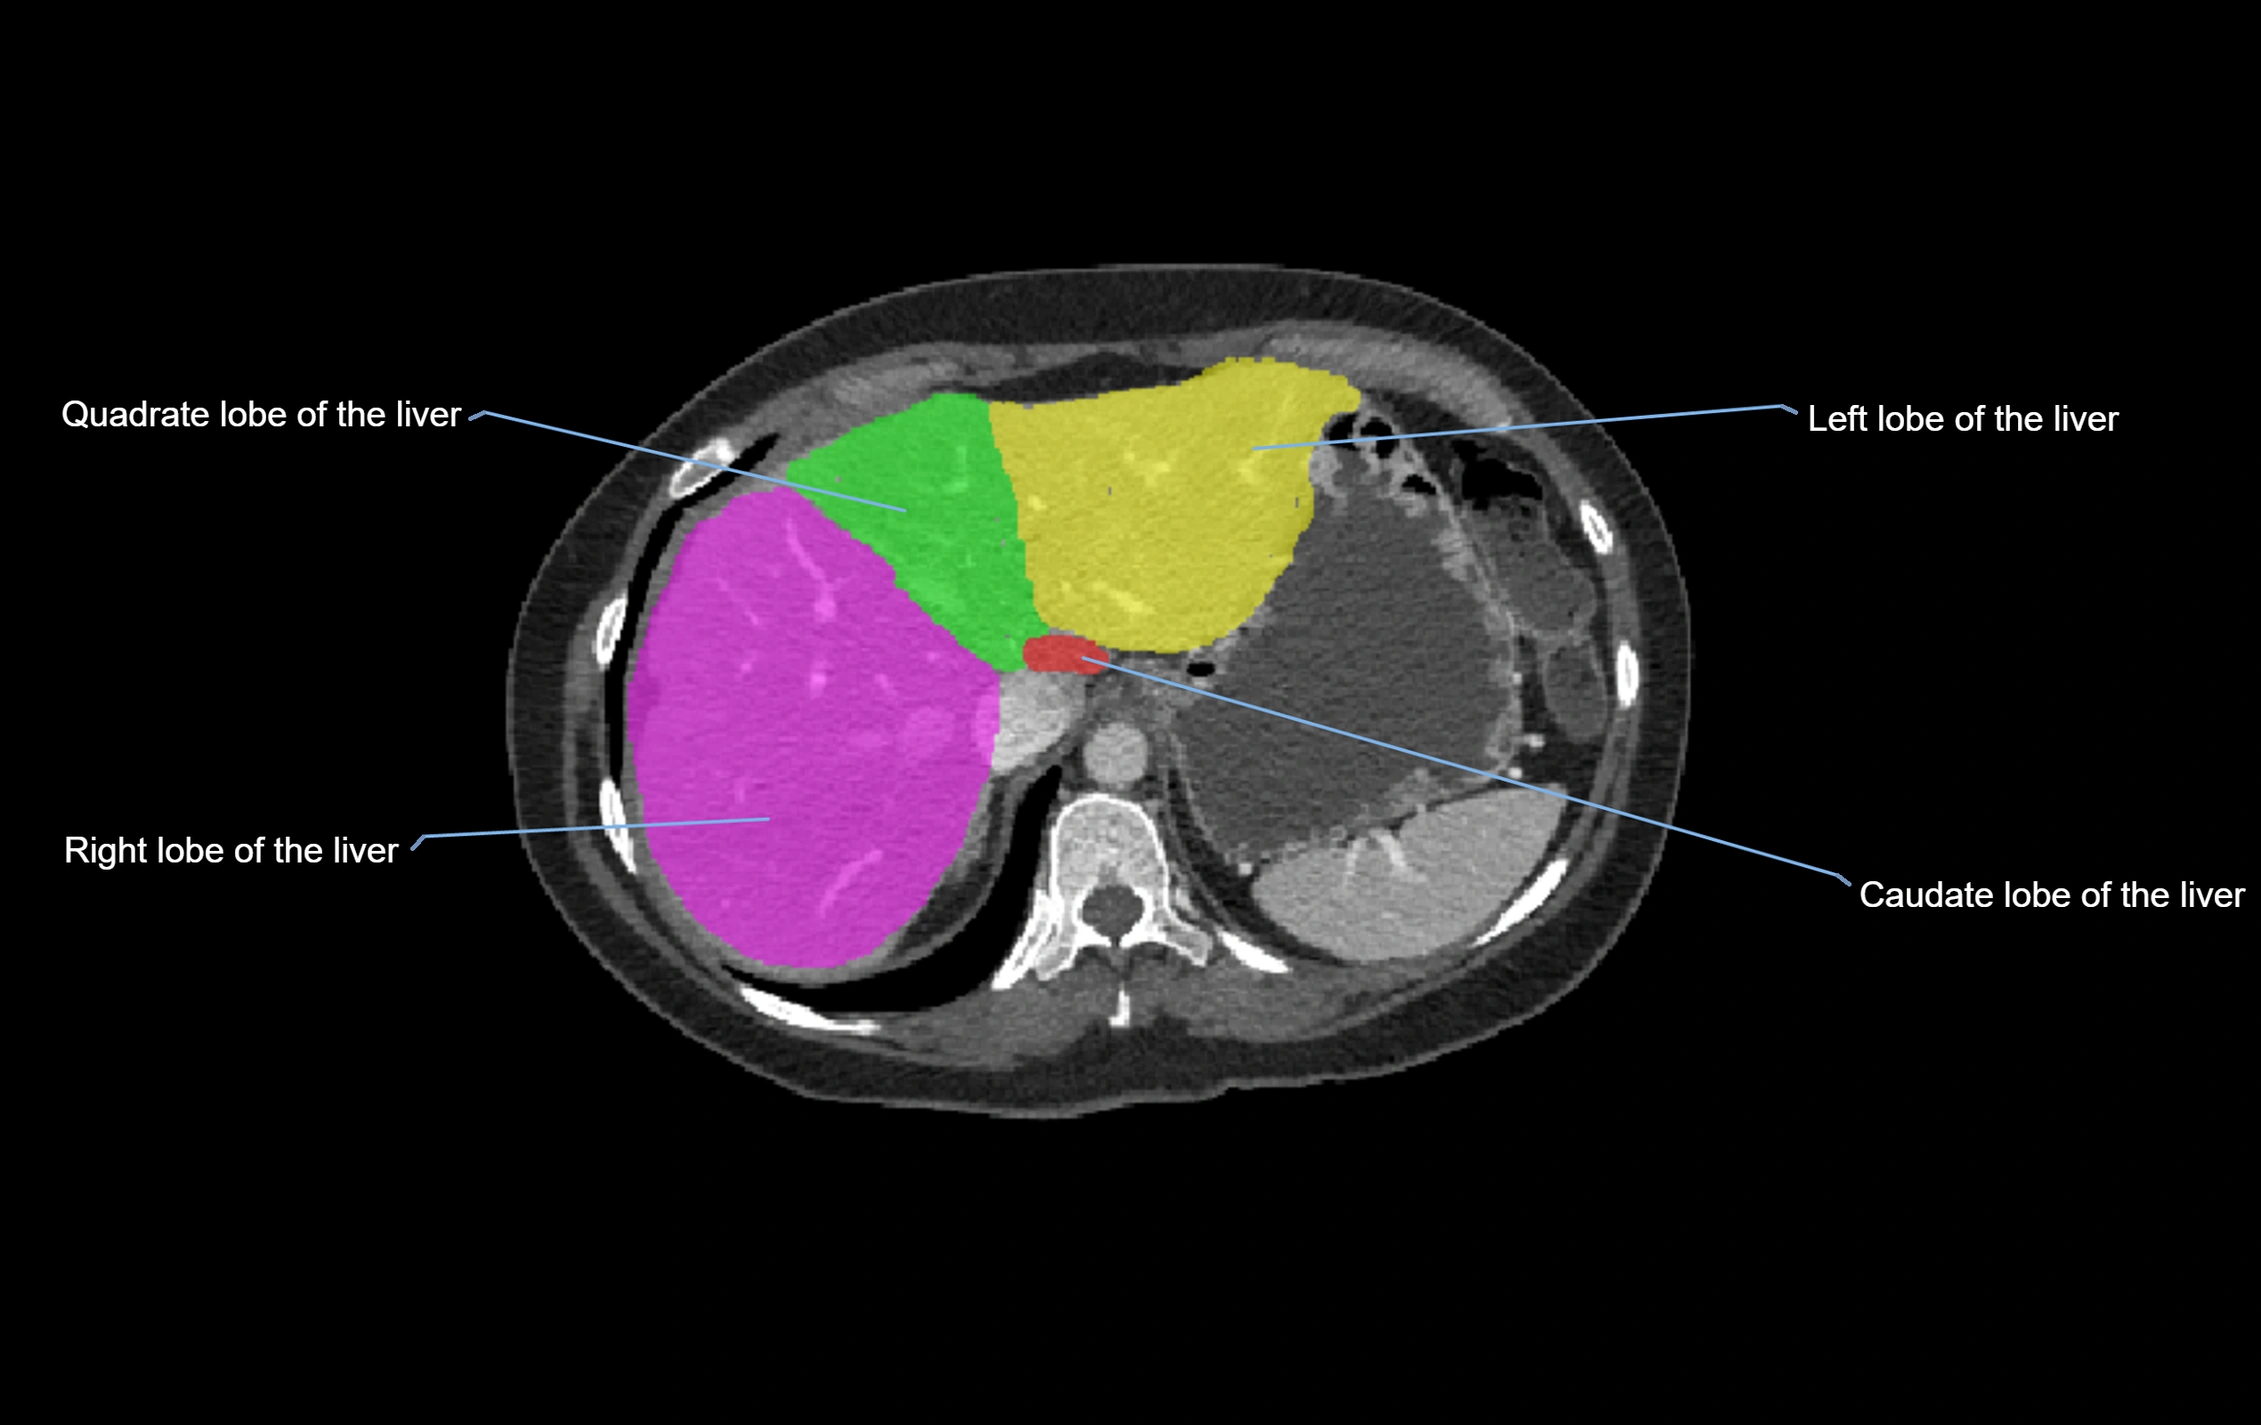

The caudate lobe of the liver is a distinct anatomical subdivision of the liver, designated as segment I in Couinaud’s classification. It lies on the posterior surface of the liver, between the fissure for the ligamentum venosum (left boundary) and the groove for the inferior vena cava (IVC) (right boundary). Superiorly, it is related to the posterior liver surface, and inferiorly it is separated from the left lobe by the porta hepatis.

CT Appearance

CT Pre-Contrast:

• Caudate lobe appears as a soft-tissue density, isodense to the rest of the liver

• Enlargement may be appreciated in cirrhosis or Budd–Chiari syndrome

CT Post-Contrast:

• Homogeneous enhancement in the portal venous phase, similar to rest of liver

• Independent venous drainage into the IVC may be visualized

• Lesions follow characteristic CT enhancement patterns (HCC: arterial hyperenhancement with washout; hemangiomas: peripheral nodular enhancement with centripetal fill-in)

CT Venous Phase (functional significance):

• Caudate lobe often enhances relatively more than other lobes in Budd–Chiari syndrome, due to preserved venous outflow

CT Image